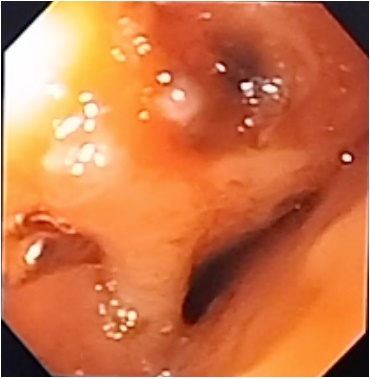

En cuanto a la técnica, se introdujo equipo de visión frontal; en los casos donde se colocaron endoclips, se localizó el orificio fistuloso, se marcaron sus límites con argón plasma (Figura 1) y en otros casos con pinza de biopsia y se procedió a liberar los clips afrontando los bordes de la fistula (Figura 2).En relación a las prótesis, se introdujo guía hidrofilica, comprobando su localización en cámara gástrica con fluoroscopia, se introdujo la prótesis metálica totalmente cubierta, quedando adecuadamente posicionada.